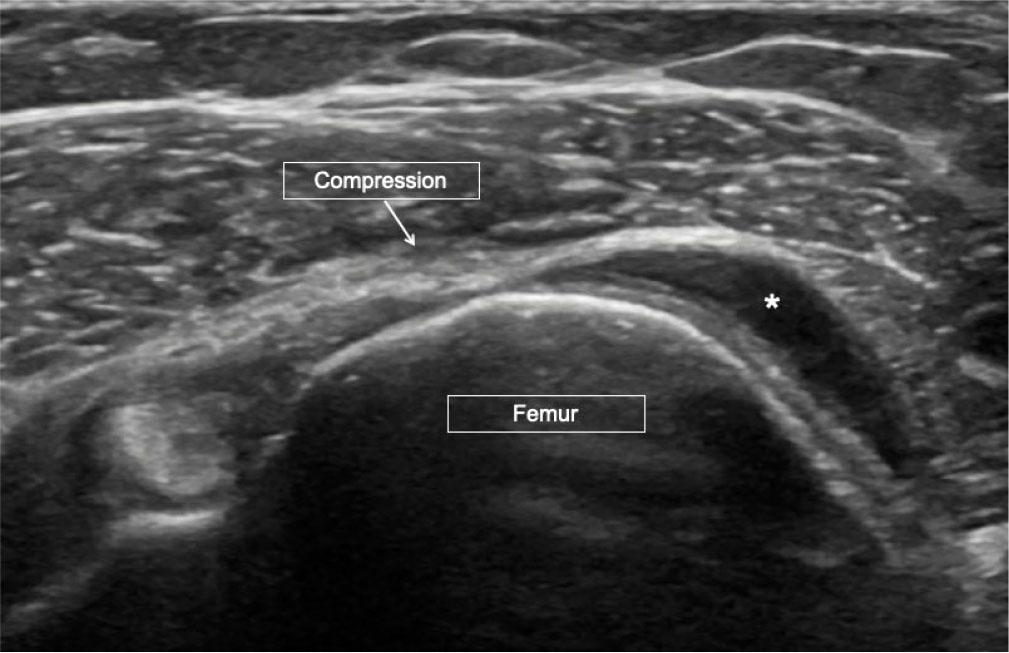

Synovial hypertrophy (SH) in US is defined as abnormal hypoechoic (relative to subdermal fat, but sometimes isoechoic or hyperechoic) intraarticular tissue that is non-displaceable and poorly compressible(4) (Fig. 2). These features help in differentiating synovial hypertrophy from joint effusion (Fig. 3).

Synovitis. Long-axis US image of the suprapatellar knee showing echogenic synovium (asterisk in A) which is partially compressible on probe pressure, as seen in image B. Arrows indicate the quadriceps tendon

Joint effusion. Short-axis US image of the shoulder joint with absent rotator cuff. Central compression (arrow) shows complete compression and displacement of the joint fluid (asterisk)